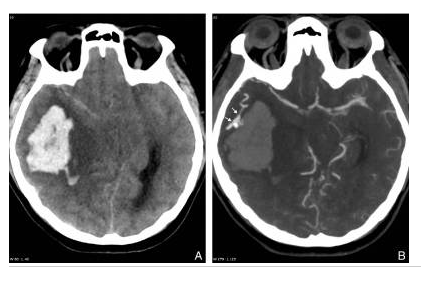

Hématome lobaire chez un sujet jeune non hypertendu en scanner.

Coupe axiale sans injection (A) : hyperdensité spontanée temporale droite responsable d’un effet de masse important. L’angioscanner (B) retrouve une prise de contraste serpigineuse (flèches) à la partie antéro-latérale de l’hématome correspondant à une malformation artérioveineuse.